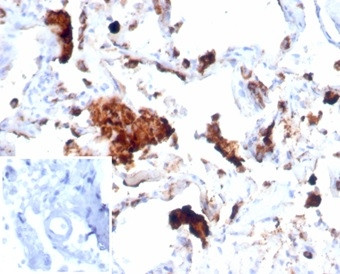

Napsin A (Lung Adenocarcinoma Marker) Antibody in Immunohistochemistry (Paraffin) (IHC (P))

Napsin A (Lung Adenocarcinoma Marker) Antibody (9476-RBM17-P1ABX) in IHC (P)

Formalin-fixed, paraffin-embedded human lung stained with Napsin A Recombinant Rabbit Monoclonal Antibody (NAPSA/7043R). Inset: PBS instead of primary antibody, secondary negative control. {{ $ctrl.currentElement.advancedVerification.fullName }} 验证信息 View more